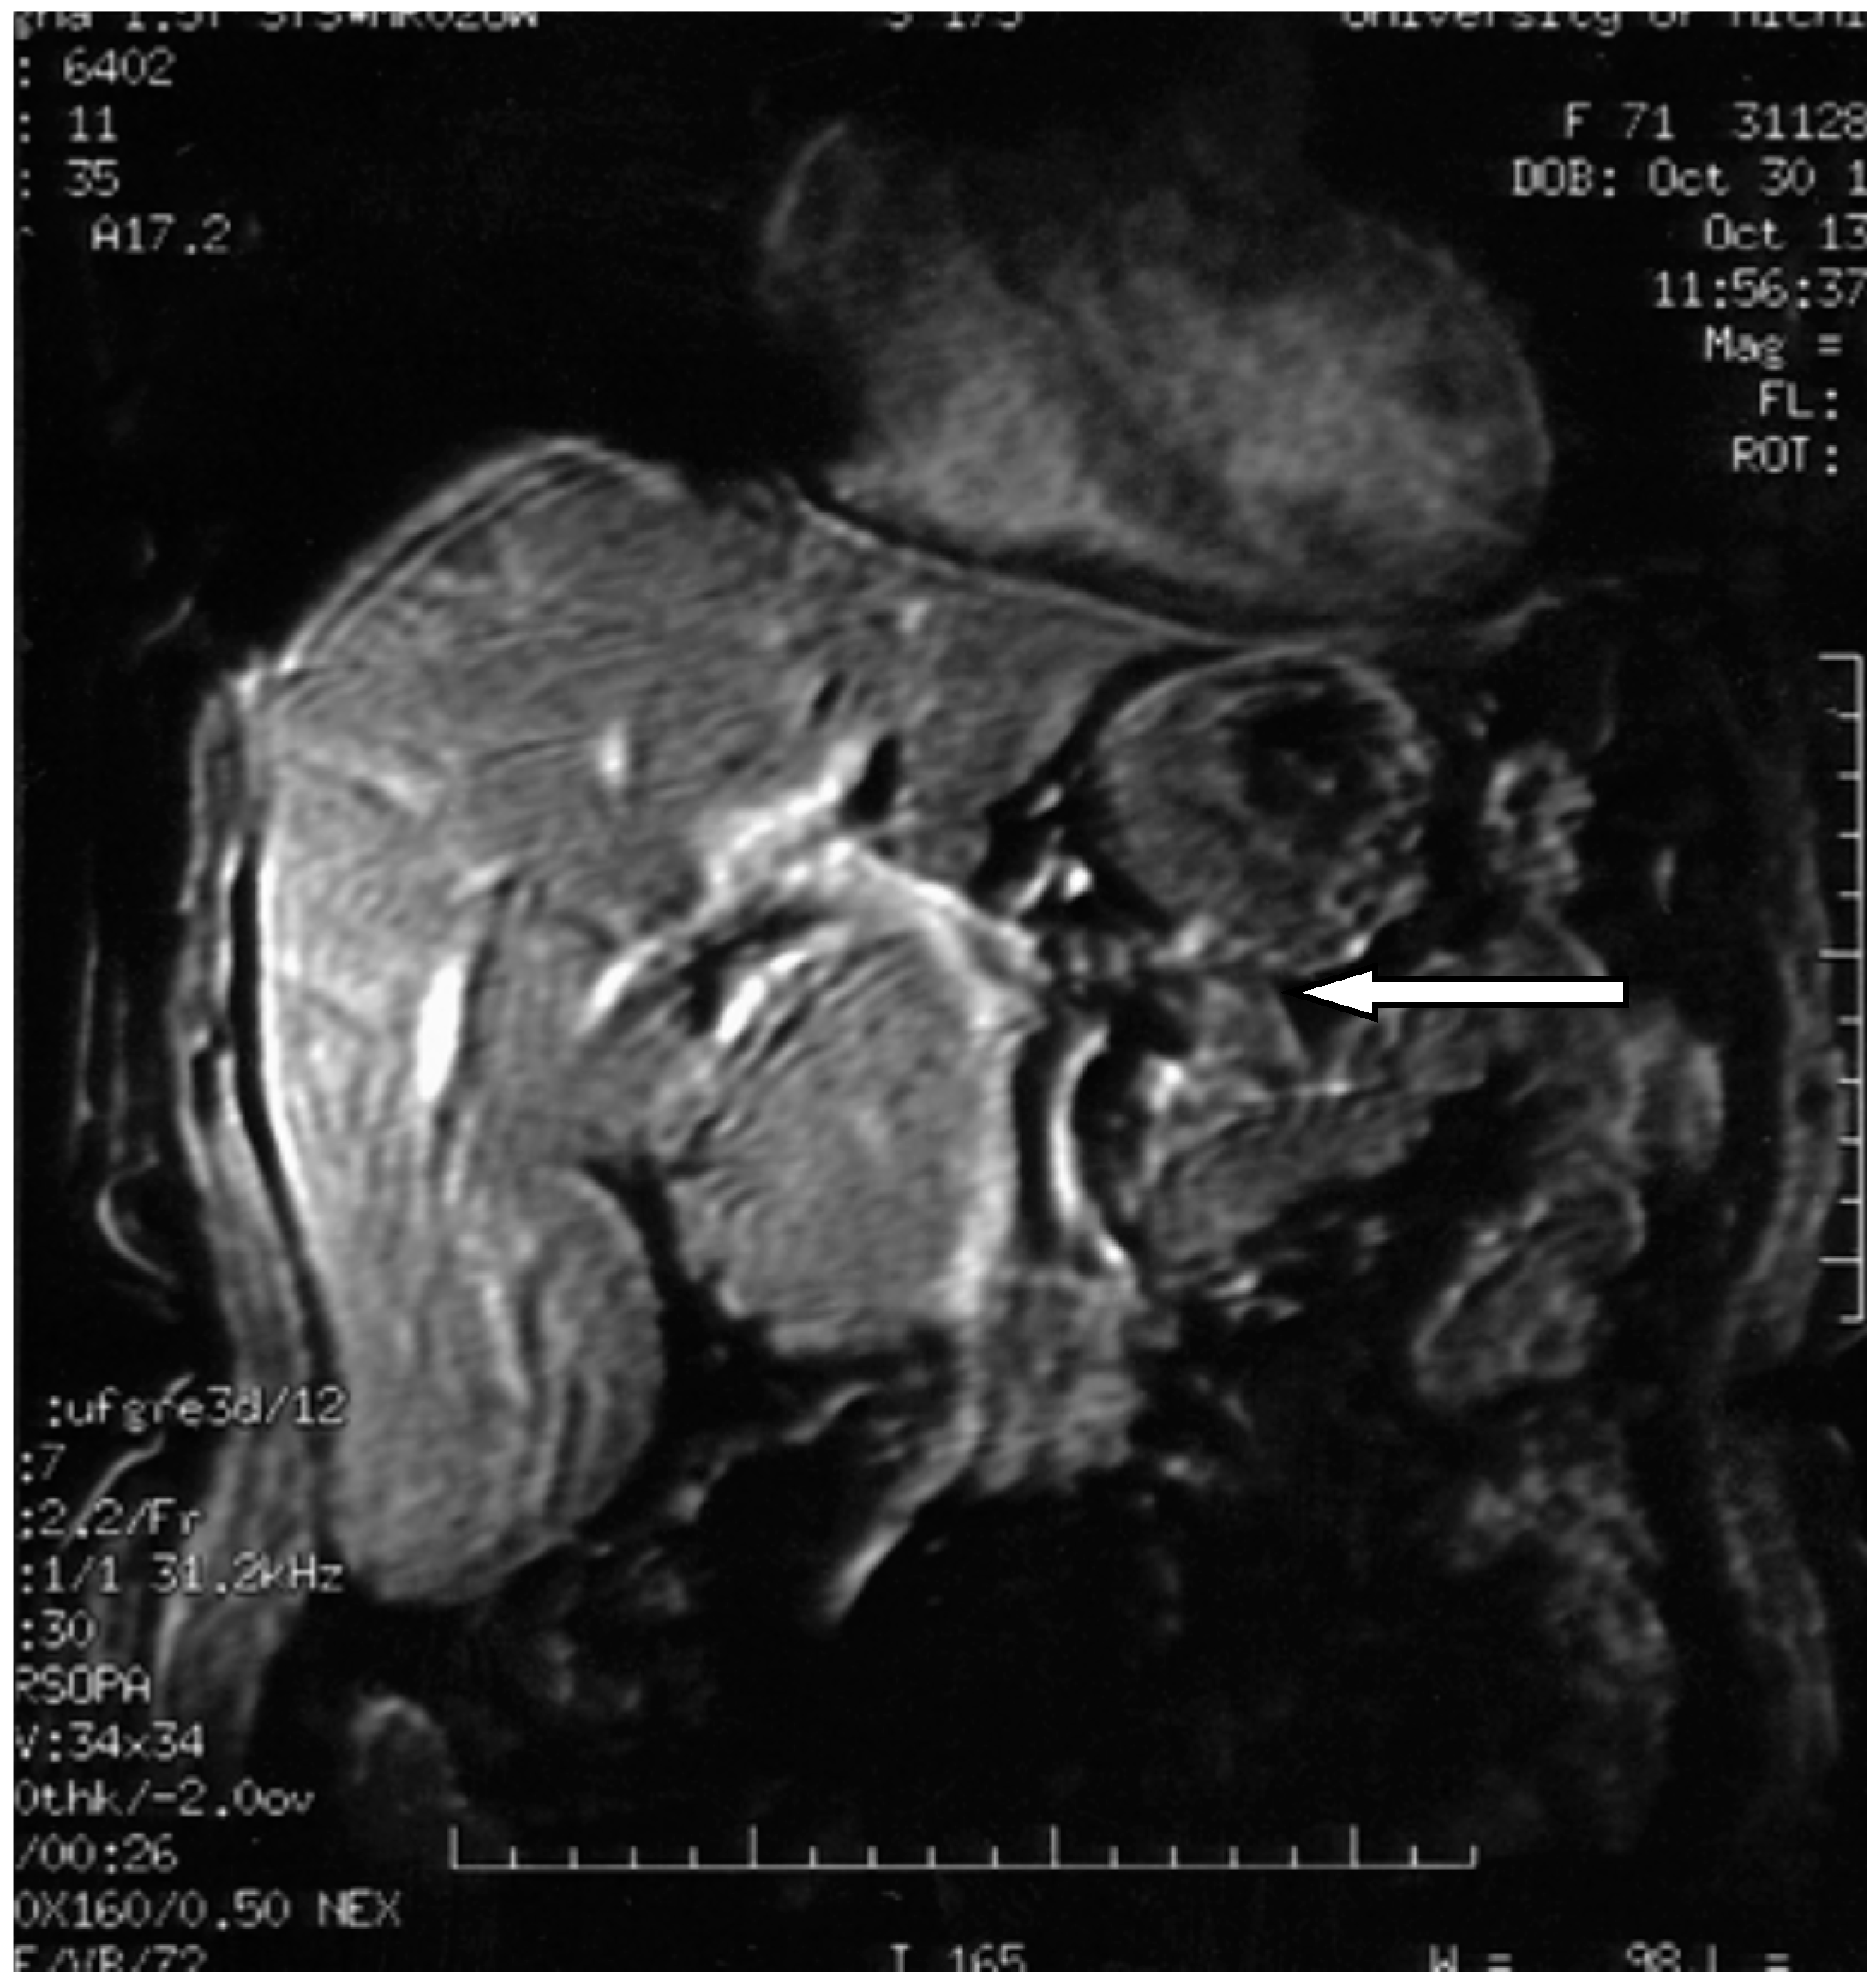

6. Diagnosis